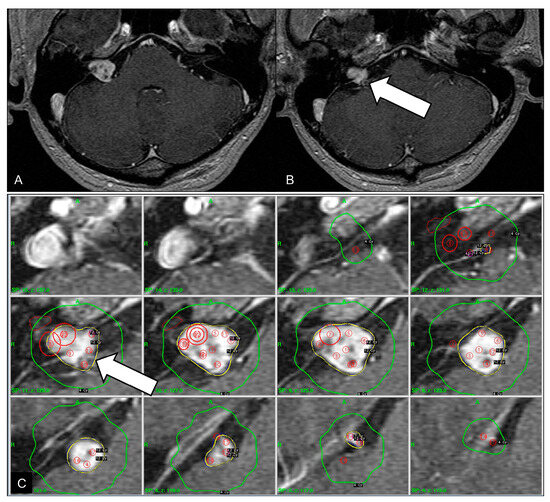

A 42-year-old man presented with a sudden onset of mental deepening. Five years ago, the patient underwent GKS for VS (Figure 1). The tumor margin was covered by the 50% isodense line, and 12 Gy was delivered to the margin. The isodense curves targeting the inferior part of the tumor compromised the neighboring AICA (Figure 1C). This vascular observation was overlooked at that time because time-of-flight magnetic resonance (TOF MR) angiography was not performed prior to GKS. He had right hearing impairment before GKS. Serial magnetic resonance images demonstrated partial regression of the tumor after GKS and did not show any vascular disorder of the neighboring AICA.

Figure 1.

Initial magnetic resonance images before gamma knife surgery. (A) Contrast-enhanced axial T1-weighted image showing a 1.5-cm vestibular schwannoma with internal necrotic content. (B) The inferior part of the vestibular schwannoma is in proximity to the neighboring anterior inferior cerebellar artery (arrow). (C) Axial dose distribution targeting the tumor, based on contrast-enhanced magnetic resonance imaging. The 12 Gy isodense line is outlined in yellow and the 4 Gy isodense line is outlined in green. The 12 Gy isodense curve encompasses the anterior inferior cerebellar artery (arrow).